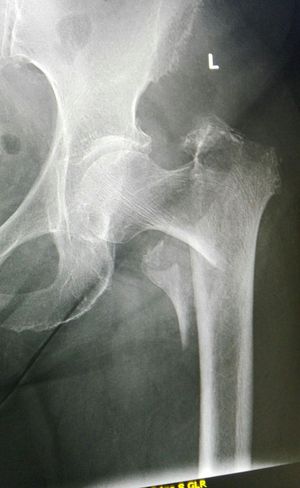

Xray

Fracture

Trohanterminor